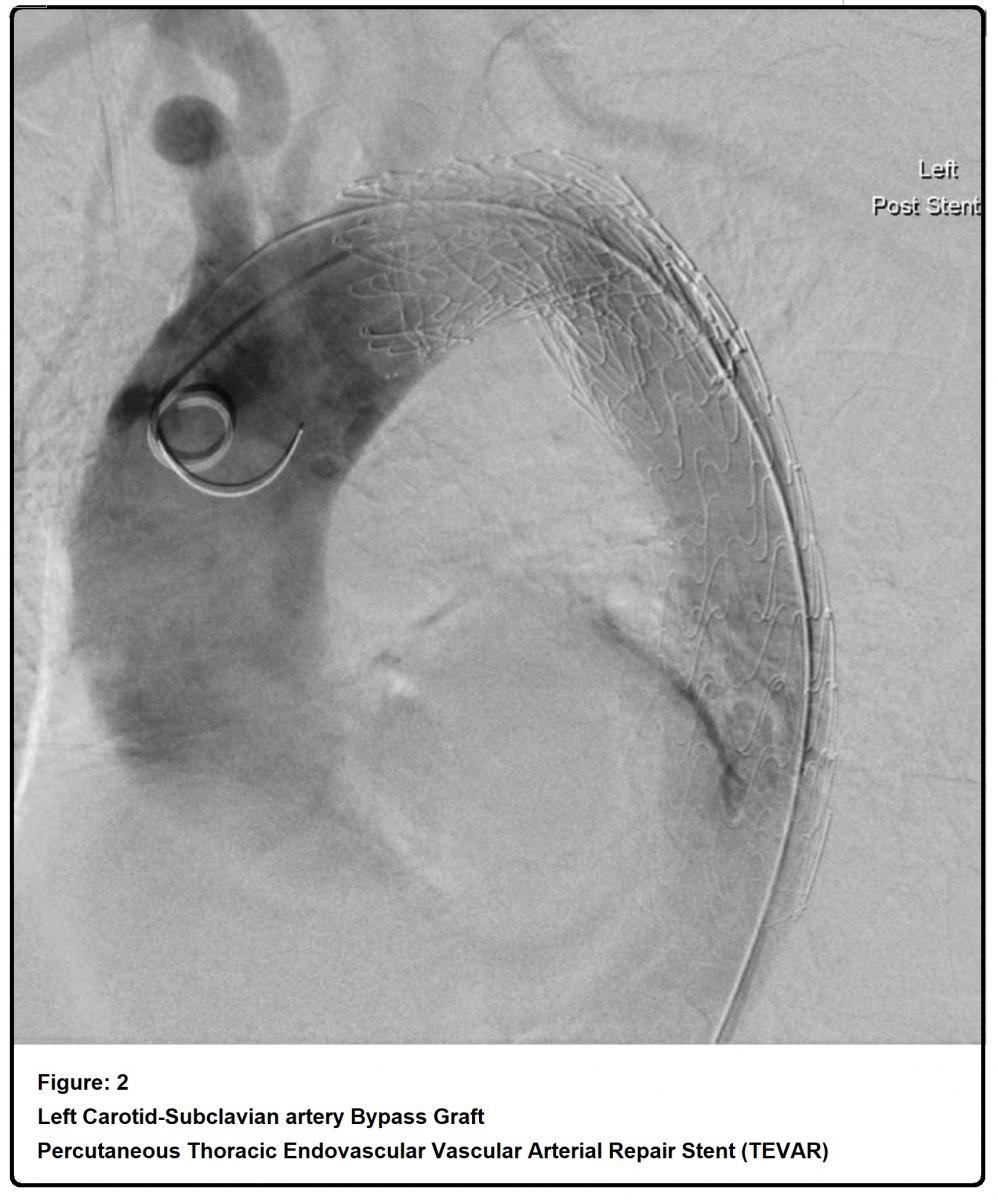

The patient in this video was a 69-year-old man who presented to the emergency department with sudden onset of chest and back pain. He was a smoker, otherwise there was no significant comorbidity, however, on admission he was markedly hypertensive. CT aorta revealed an acute type B dissection with an entry tear at the origin of the left subclavian artery; left kidney was malperfused and true lumen was significantly compressed by the false lumen (Figure 1). He developed acidosis that was a sign of organs ischaemia. He underwent emergency procedures that included left carotid-subclavian arteries bypass graft with 6 mm Dacron graft and percutaneous thoracic endovascular arterial repair in Ishimaru's zone 2, 3, 4 (TEVAR-Stent; Conformable GORE® Thoracic Endoprosthesis) (Figure 2). He was discharged on the sixth postoperative day in good condition. Subsequent CT scan showed the diameter of the ascending aorta 53 mm, while coronary angiogram revealed LAD stenosis (tight stenosis just before septal branch, moderate disease in mid segment), LCX stenosis (severe disease in LCX mid vessel), and RCA stenosis (Occluded at middle with distal collateral) (Figure 3). Transthoracic echocardiogram showed trivial aortic regurgitation, 39 mm sinus diameter and normal LV & RV systolic function.